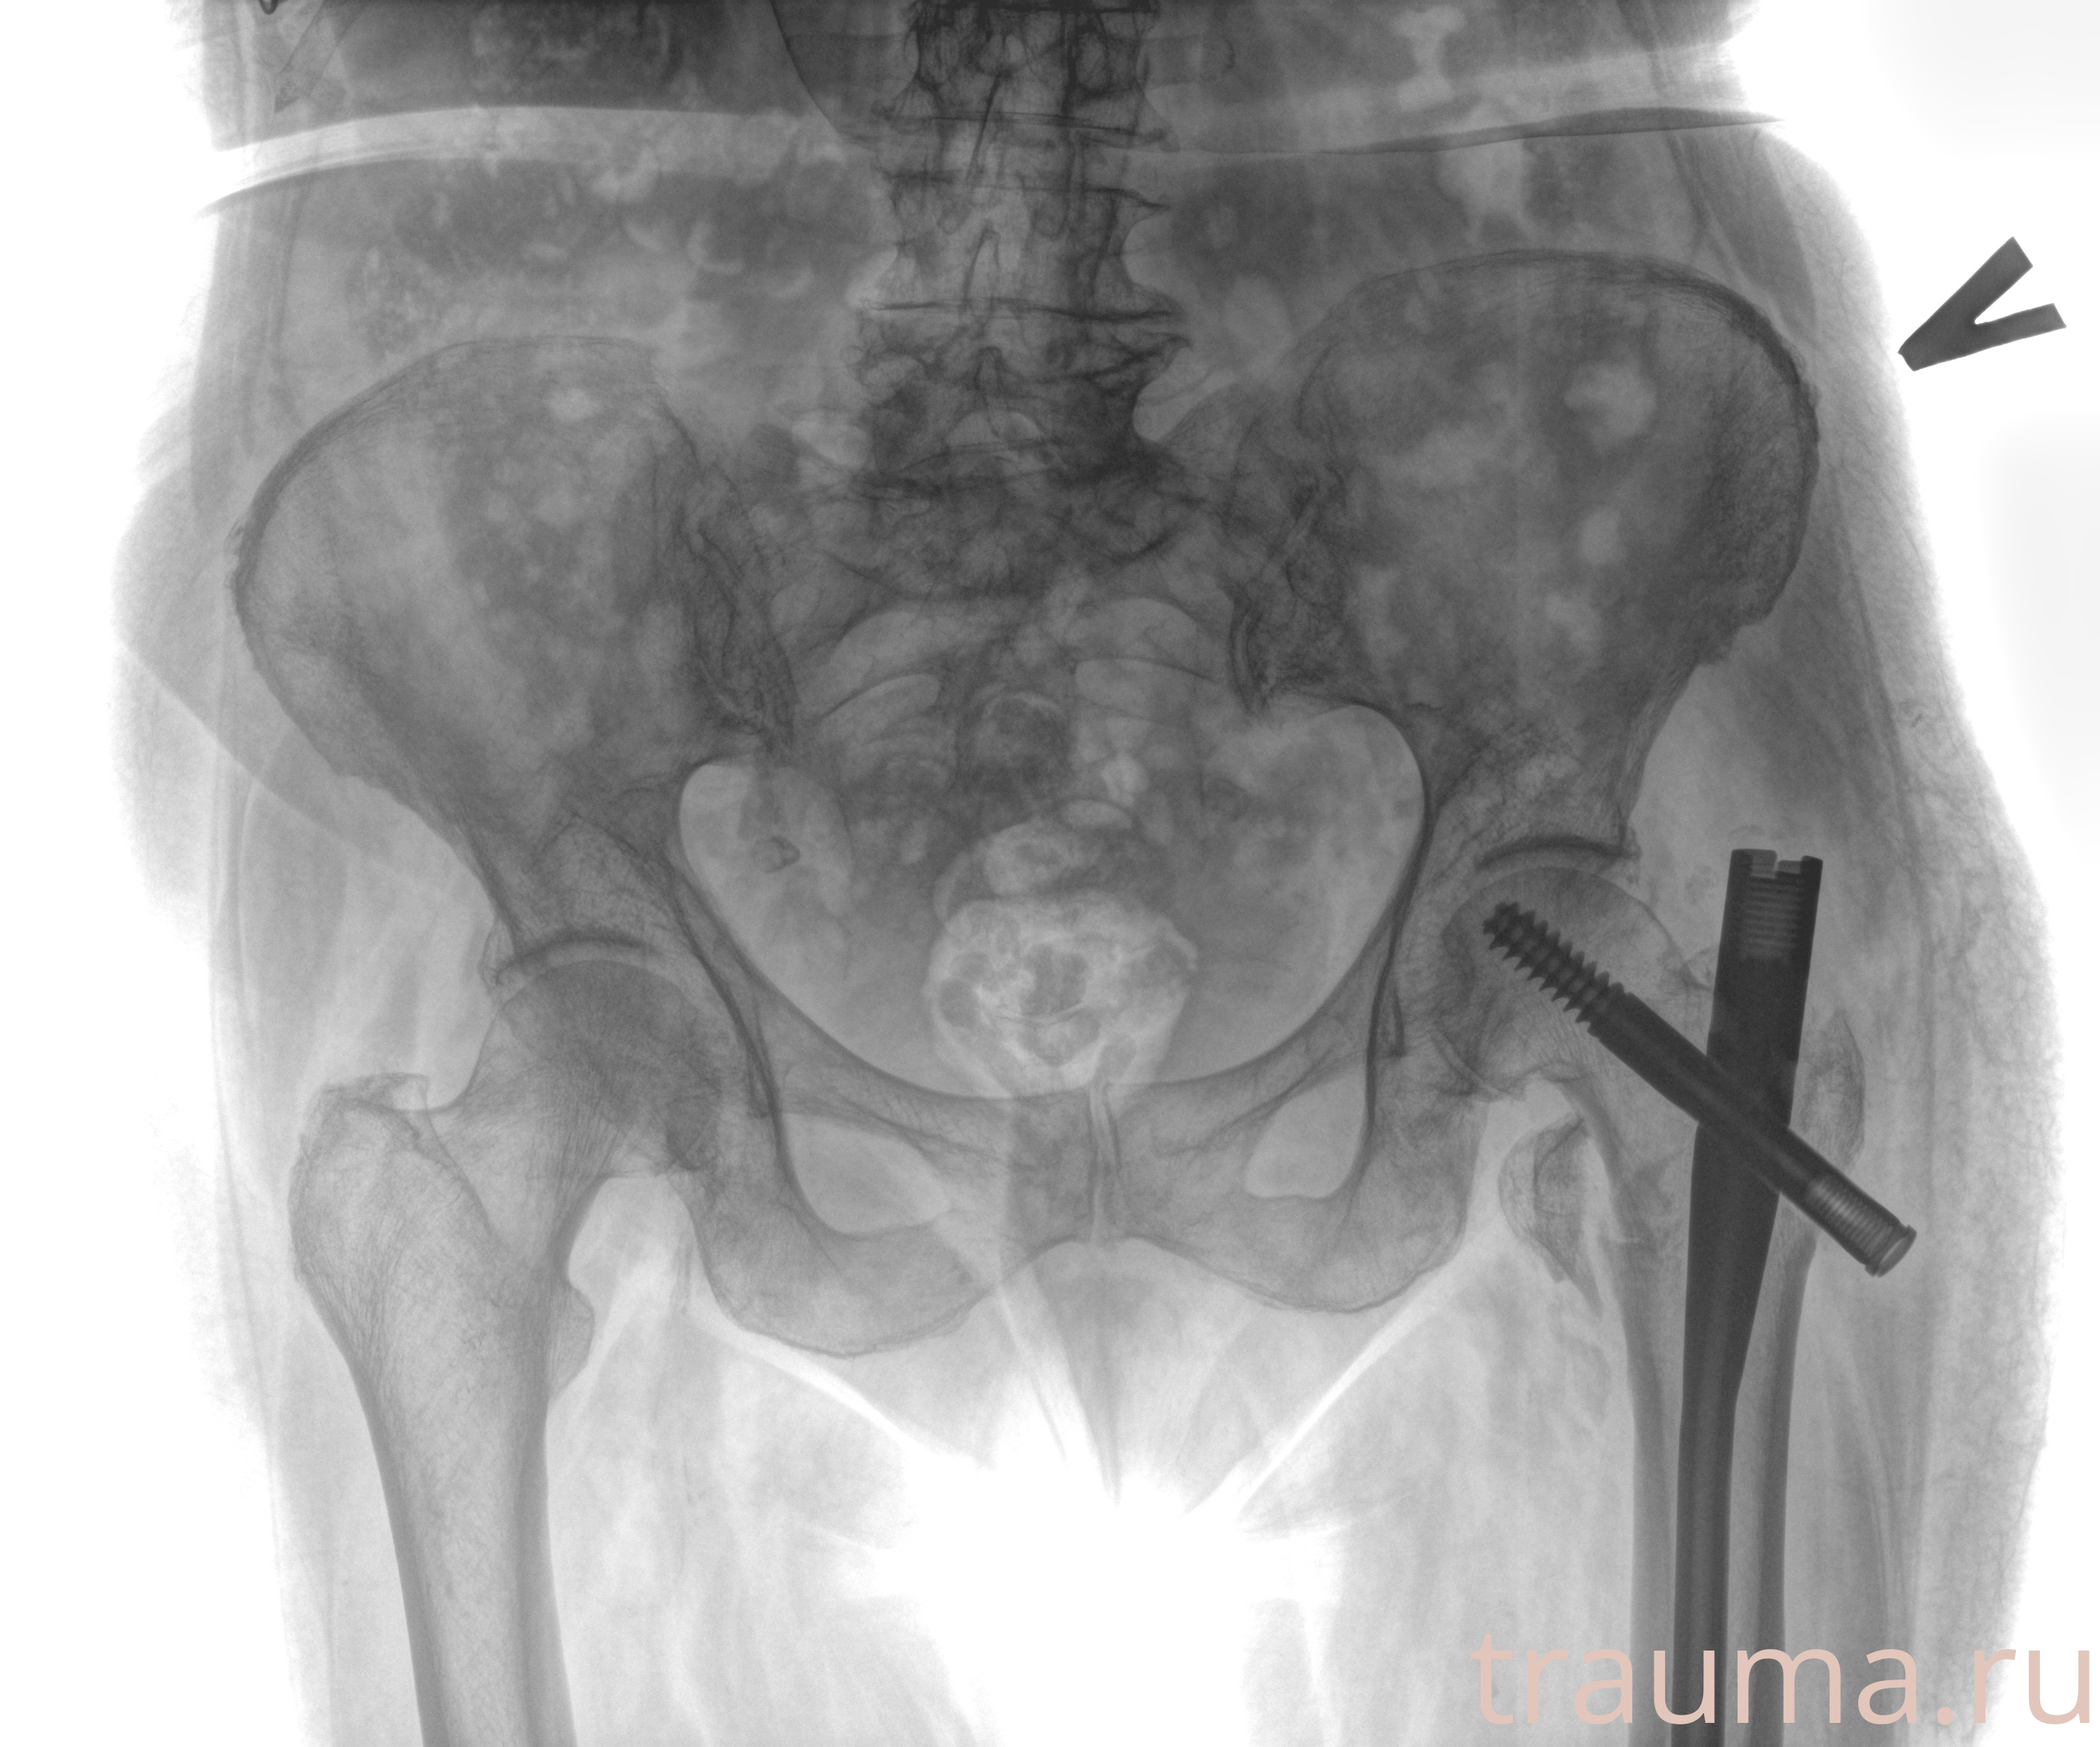

Рентгенограммы

Рентген на дому: по вашему адресу приезжает врач-рентгенолог, травматолог-ортопед с мобильным рентгеновским аппаратом, проводит диагностику травмы или заболевания, делает необходимые рентгенограммы, дает рекомендации по дальнейшему лечению. Получить качественные снимки в домашних условиях возможно благодаря уникальной методике, разработанной МосРентген Центром для института  Склифосовского